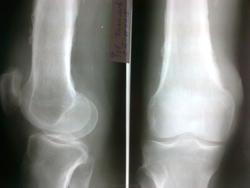

Здравствуйте, коллеги. Помогите с диагностикой. Больной 1954 г.р. пришел от врача-терапевта с направлением "остеоартроз левого коленного сустава", жалуется на боли, со слов год назад получил травму. Профессия-пастух.

Имеется поражение всего медадиафиза бедренной кости с переоссальными наслоениями, утолщение кортикального слоя. Наличие очага деструкции в н\3 бедренной кости без четкого контура с наличием остесклеротического вала. По моему увеличение плотности мягких тканей. Округлый дефект? в проекции межмыщелкового возвышения б\б коости с зоной остеосклероза. Первично хронический остеомиелит б\б кости?

Периостоз похож на Бамбергера-Мари, но остеолизиз здесь не укладывается. На фиброзно-кортикальный дефект не очень тянет (хотя в много ходящего пешком пастуха может быть). Остеолитические метастазы, скорее. Полный онкопоиск. РГ ОГК обязательно.

Вот две флюорограммы с архива, одна свежая от 19 марта2013 года, где был выставлен Инфильтративный туберкулез в S2-S3 правого легкого. Послеоперационная гипотрофия левого легкого. Со слов больного перенес операцию по поводу кавернозного тбс в левом легком.

Периферический рак с мтс в кости получается. У меня недавно похожий случай был.

Только в вашем случае еще посттуберкулезные изменения добавляются.